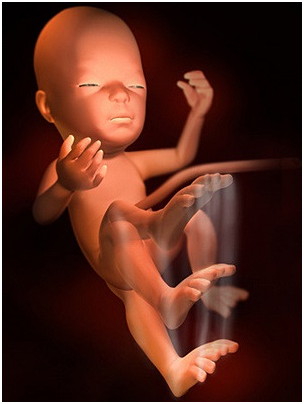

怀孕第8周如果还没检查过的准妈妈,这周一定要开始第一次产前检查啦!胎儿的胚胎器官已经开始具...

怀孕第8周如果还没检查过的准妈妈,这周一定要开始第一次产前检查啦!胎儿的胚胎器官已经开始具... -